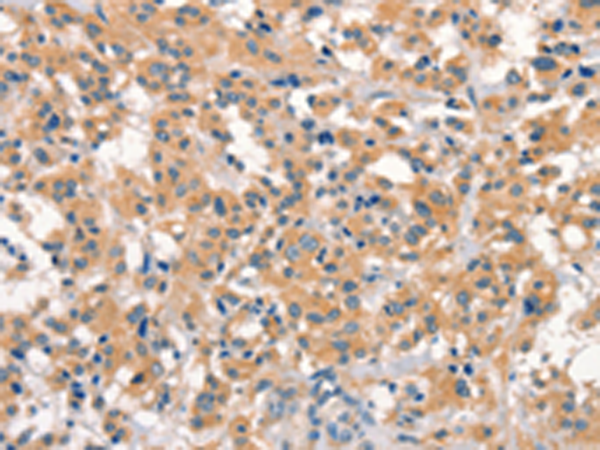

分类: 科研抗体货号: P04893别名:应用: WB,IHC反应种属: Human, Mouse